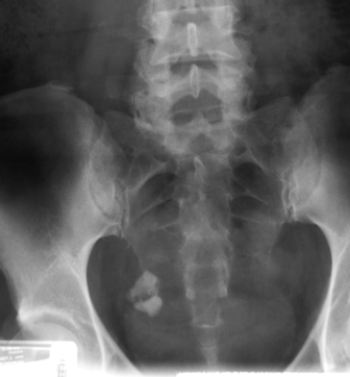

Male and Female Urinary Tract and Male Genital Tract